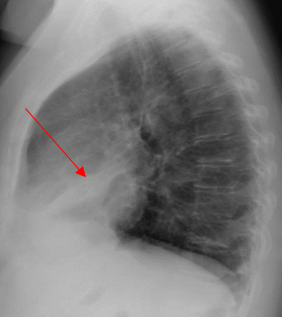

A 52-year-old Caucasian female, who is a resident of southwestern Ohio, presented to the emergency room with a chief complaint of a two-week history of right-sided chest pain, which had progressively worsened despite two courses of antibiotics and pain medications following her two recent visits to the emergency department. She also described subjective fever, shortness of breath, nonproductive cough and weight loss of 4 kg over the last two weeks. She was a smoker of ½ pack per day for 20 years and quit smoking 4 weeks ago. The patient’s past medical history includes anxiety, depression, gastroesophageal reflux disease, hypertension, mitral valve prolapse, and migraine headache. Her chest pain started in early September, and it was described as stabbing and pleuritic, which was also noted to be reproducible to palpation of the chest wall. She was seen first at the emergency department two weeks prior to the current presentation for evaluation of the right-sided chest pain. Still, at that time, there was no fever or cough, and her vitals were stable with Oxygen Saturation 94% on room air, although her laboratory testing was significant for leukocytosis with (WBC):16.6 K/UL with 68.5% neutrophils. Chest-X-ray demonstrated an infiltrate in the right lung base medially, while CT–chest angiography demonstrated no evidence of pulmonary embolism and right middle lobe consolidation consistent with pneumonia. There was no mediastinal or hilar lymphadenopathy, (Figures 1 and 2).

Figure 2. CT-chest angiography showing right middle lobe consolidation.